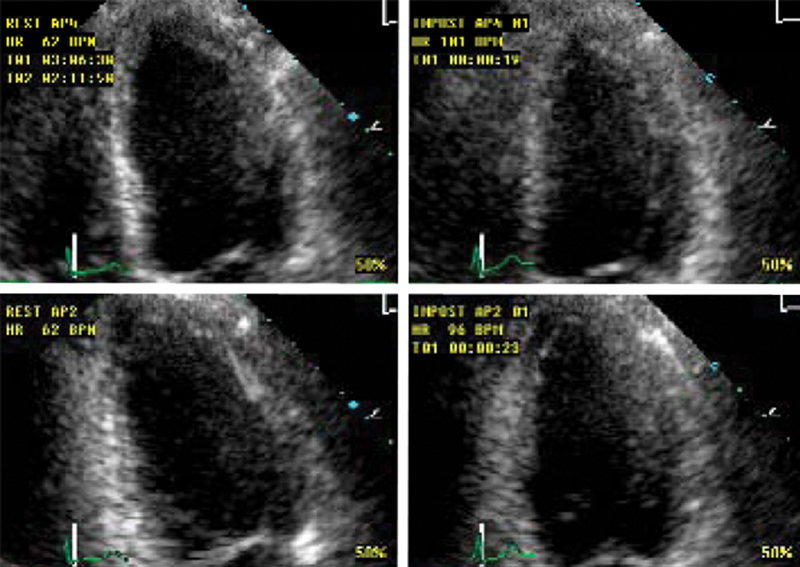

فحوصات تشخيصية لبعض امراض القلب والشرايين التاجية